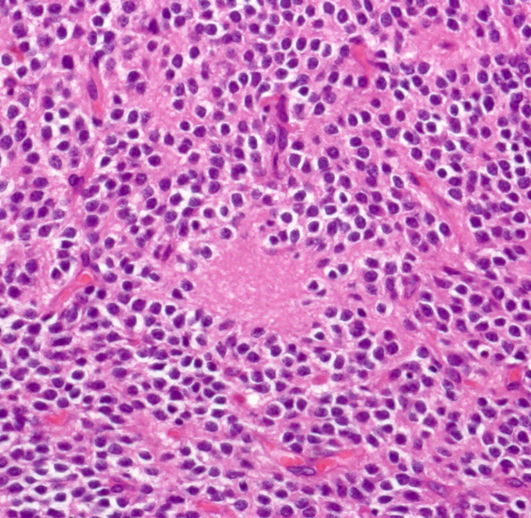

病理所見

石灰化(画面右側の紫色の部分)とともに、均一な大きさの円形の核を有する腫瘍細胞が敷石状に配列している。

核周囲は明るく抜けている。腫瘍細胞間には細い血管が介在し、腫瘍細胞を区画している。

腫瘍細胞間には好酸性(ピンク色)の細線維性基質が認められる。

免疫染色(Olig2)。HE染色で核周囲が明るく抜ける形態からoligodendrogliomaが鑑別となるが、Olig2は陰性で、oligodendrogliomaは否定される。

免疫染色(Synaotphysin:神経内分泌marker)。腫瘍細胞間の細線維性基質に陽性を示す。

下は,病理像です。均一な丸い核を持った細胞が密に配列していますがPNETのような未分化腫瘍ではなくて良性の腫瘍です。ちょっと見には乏突起膠腫にとても似ているので,1980年代までは脳室内乏突起膠腫 (intraventricular oligodendroglioma) と呼ばれていました。シナプトフィジンやNSEという特殊染色で染まるので確定病理診断がつきます。